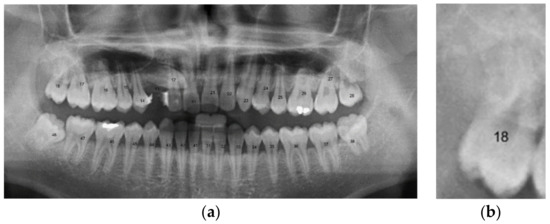

2.2.3. Positioning Numbers

3. Results

| 18 | True | True |

| 17 | True | True |

| 16 | True | True |

| 15 | False | True |

| 14 | False | True |

| 13 | True | True |

| 12 | True | True |

| 11 | True | True |